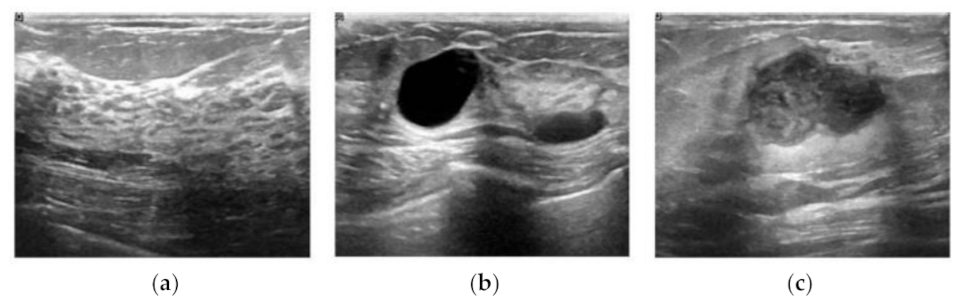

Although US imaging is one of the most popular modalities in practical clinical applications, it is difficult to find publicly available US image datasets in the literature. The dataset used in this study was recently released to the public, which consists of breast US images from 600 female patients aged between 25 and 75 years at the Baheya hospital in 2018 [15]. The data were acquired using the LOGIQ E9 ultrasound system and LOGIQ E9 Agile ultrasound system with the ML6-15-D matrix linear transducer, and converted gray scale images were obtained with an average size of 500 × 500 in PNG file format. The dataset consists of 780 B-mode images with pathological status and is categorized into three classes: normal, benign, and malignant. The numbers of images for the three classes are presented in Table 1, and the sample US images of each class are shown in Figure 1.

Figure 1.

Sample B-mode images of the breast ultrasounddataset [11]; (a) Normal, (b) benign, and (c) malignant.